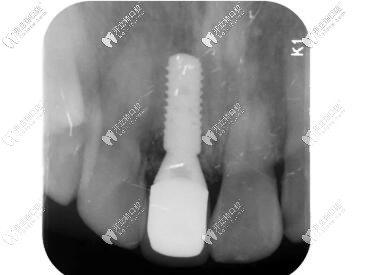

影像學(xué)檢查

門牙磕斷傷及牙根影像學(xué)檢查

被磕的牙冠根向折裂,直達(dá)骨下;

牙根骨量充足;

牙長(zhǎng)軸和牙槽骨的方向基本一致。

術(shù)后CBCT顯示植入正確的三維位置,種植體唇側(cè)骨量充足;

瑞士iti鈦親水BL 4.1mm*10mm種植體